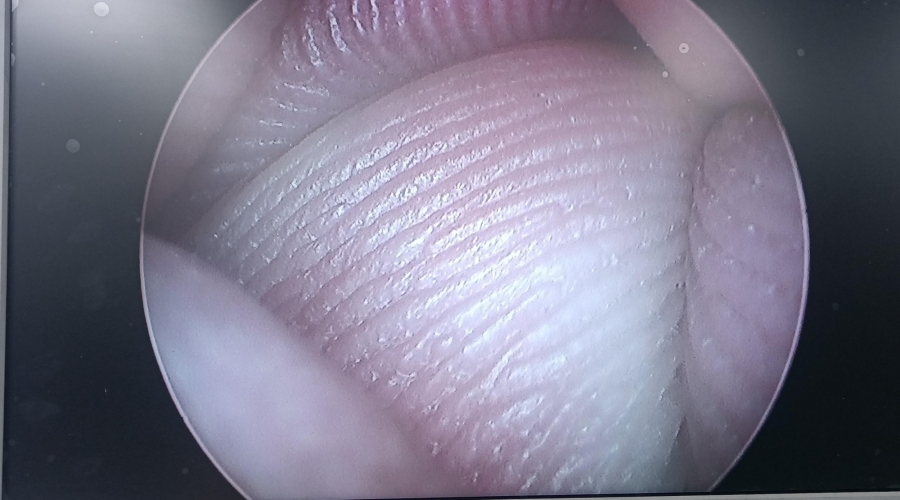

電切鏡的介紹及Wolf狼牌電切鏡8650.414維修案例分析

設備型號Wolf狼牌電切鏡8650.414

故障內容圖像模糊,棒透鏡破碎,導光錐破碎,目鏡罩破碎,鏡身有磕碰,但不影響使用。

維修方案更換棒透鏡、導光錐、目鏡罩,校對圖像,內窺鏡抗震蕩抗沖擊性能測試,內窺鏡密封性性能檢測;內窺鏡抗震蕩性能測試,內窺鏡冷熱沖擊性能檢測。